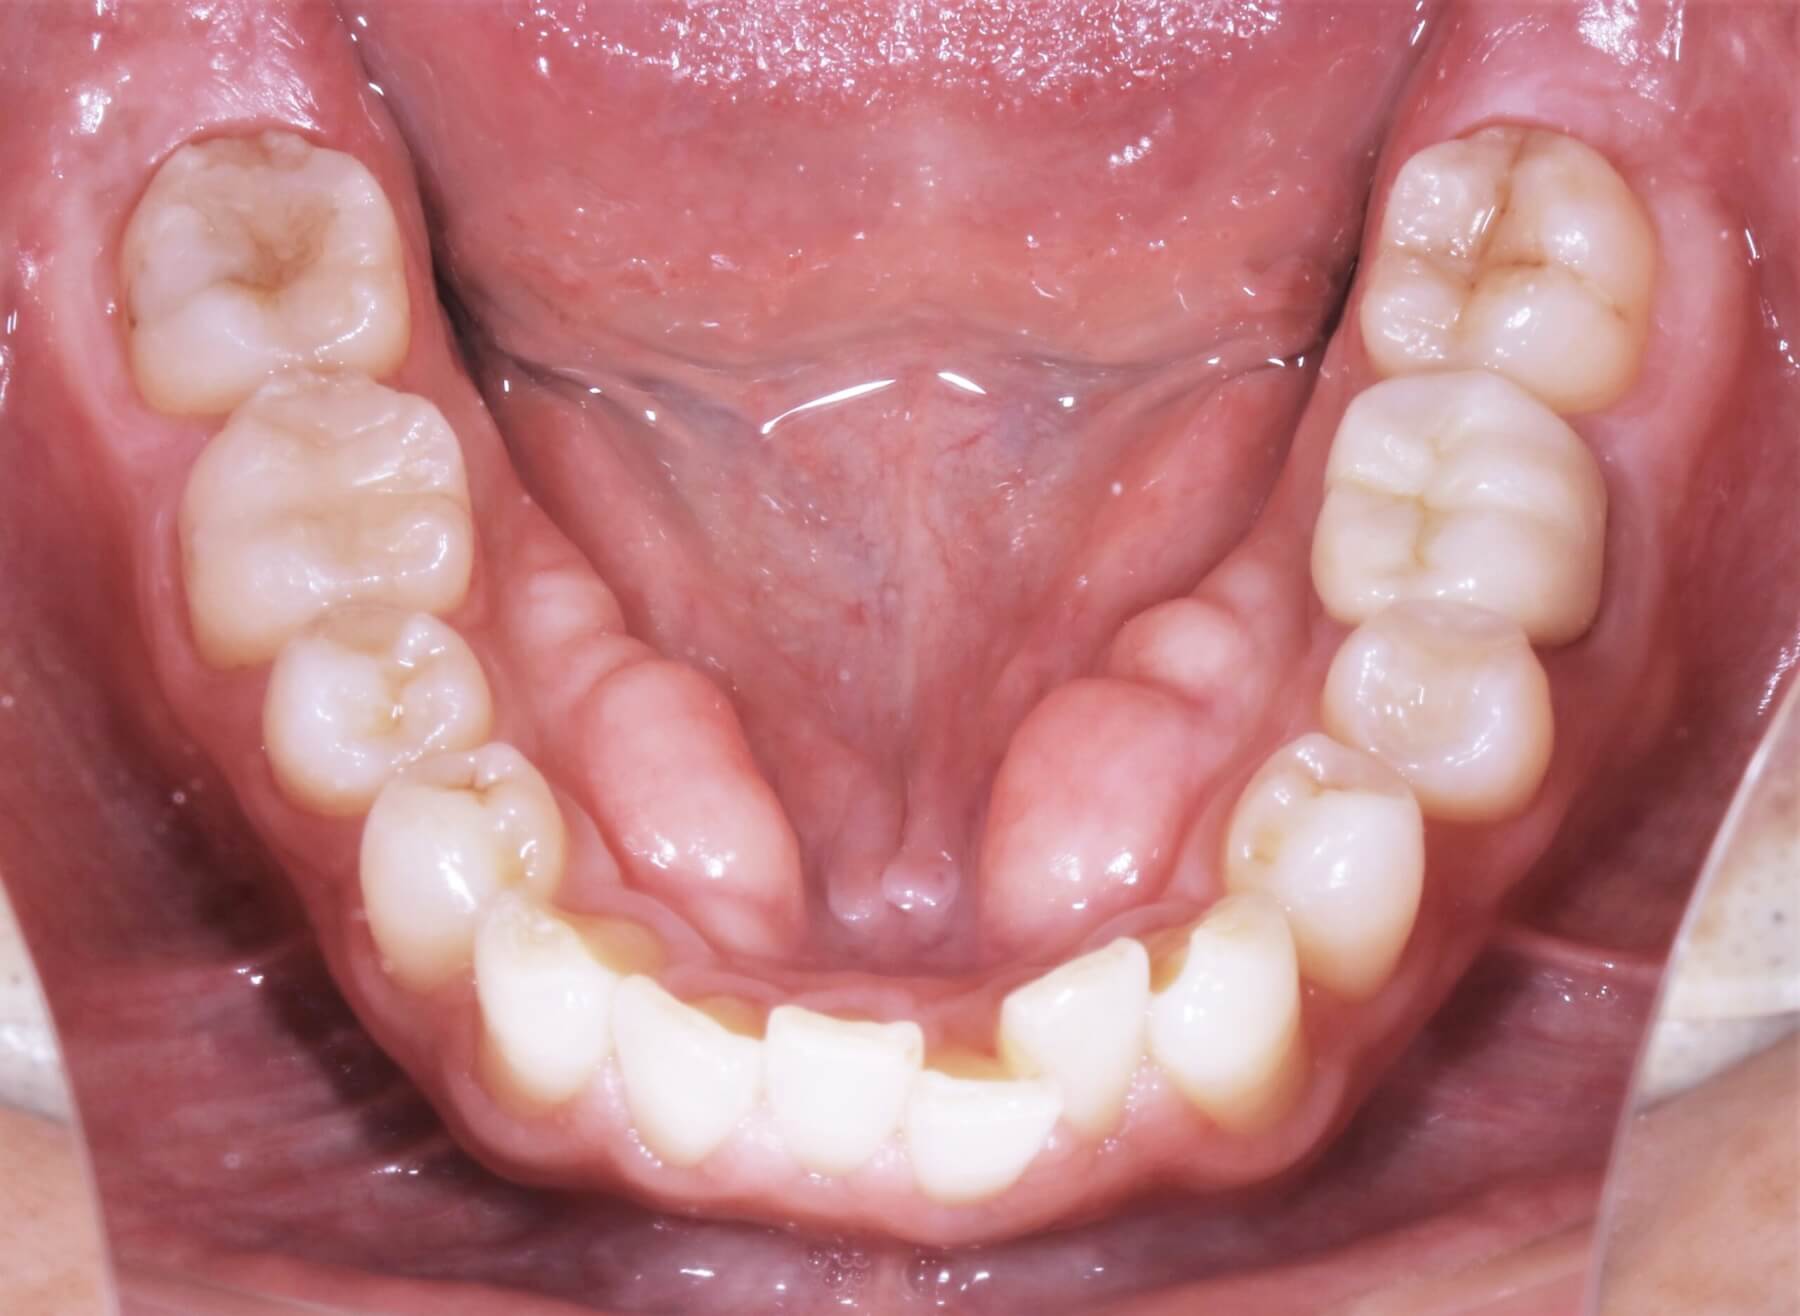

▲下顎隆起

下顎隆起症例

▼治療前